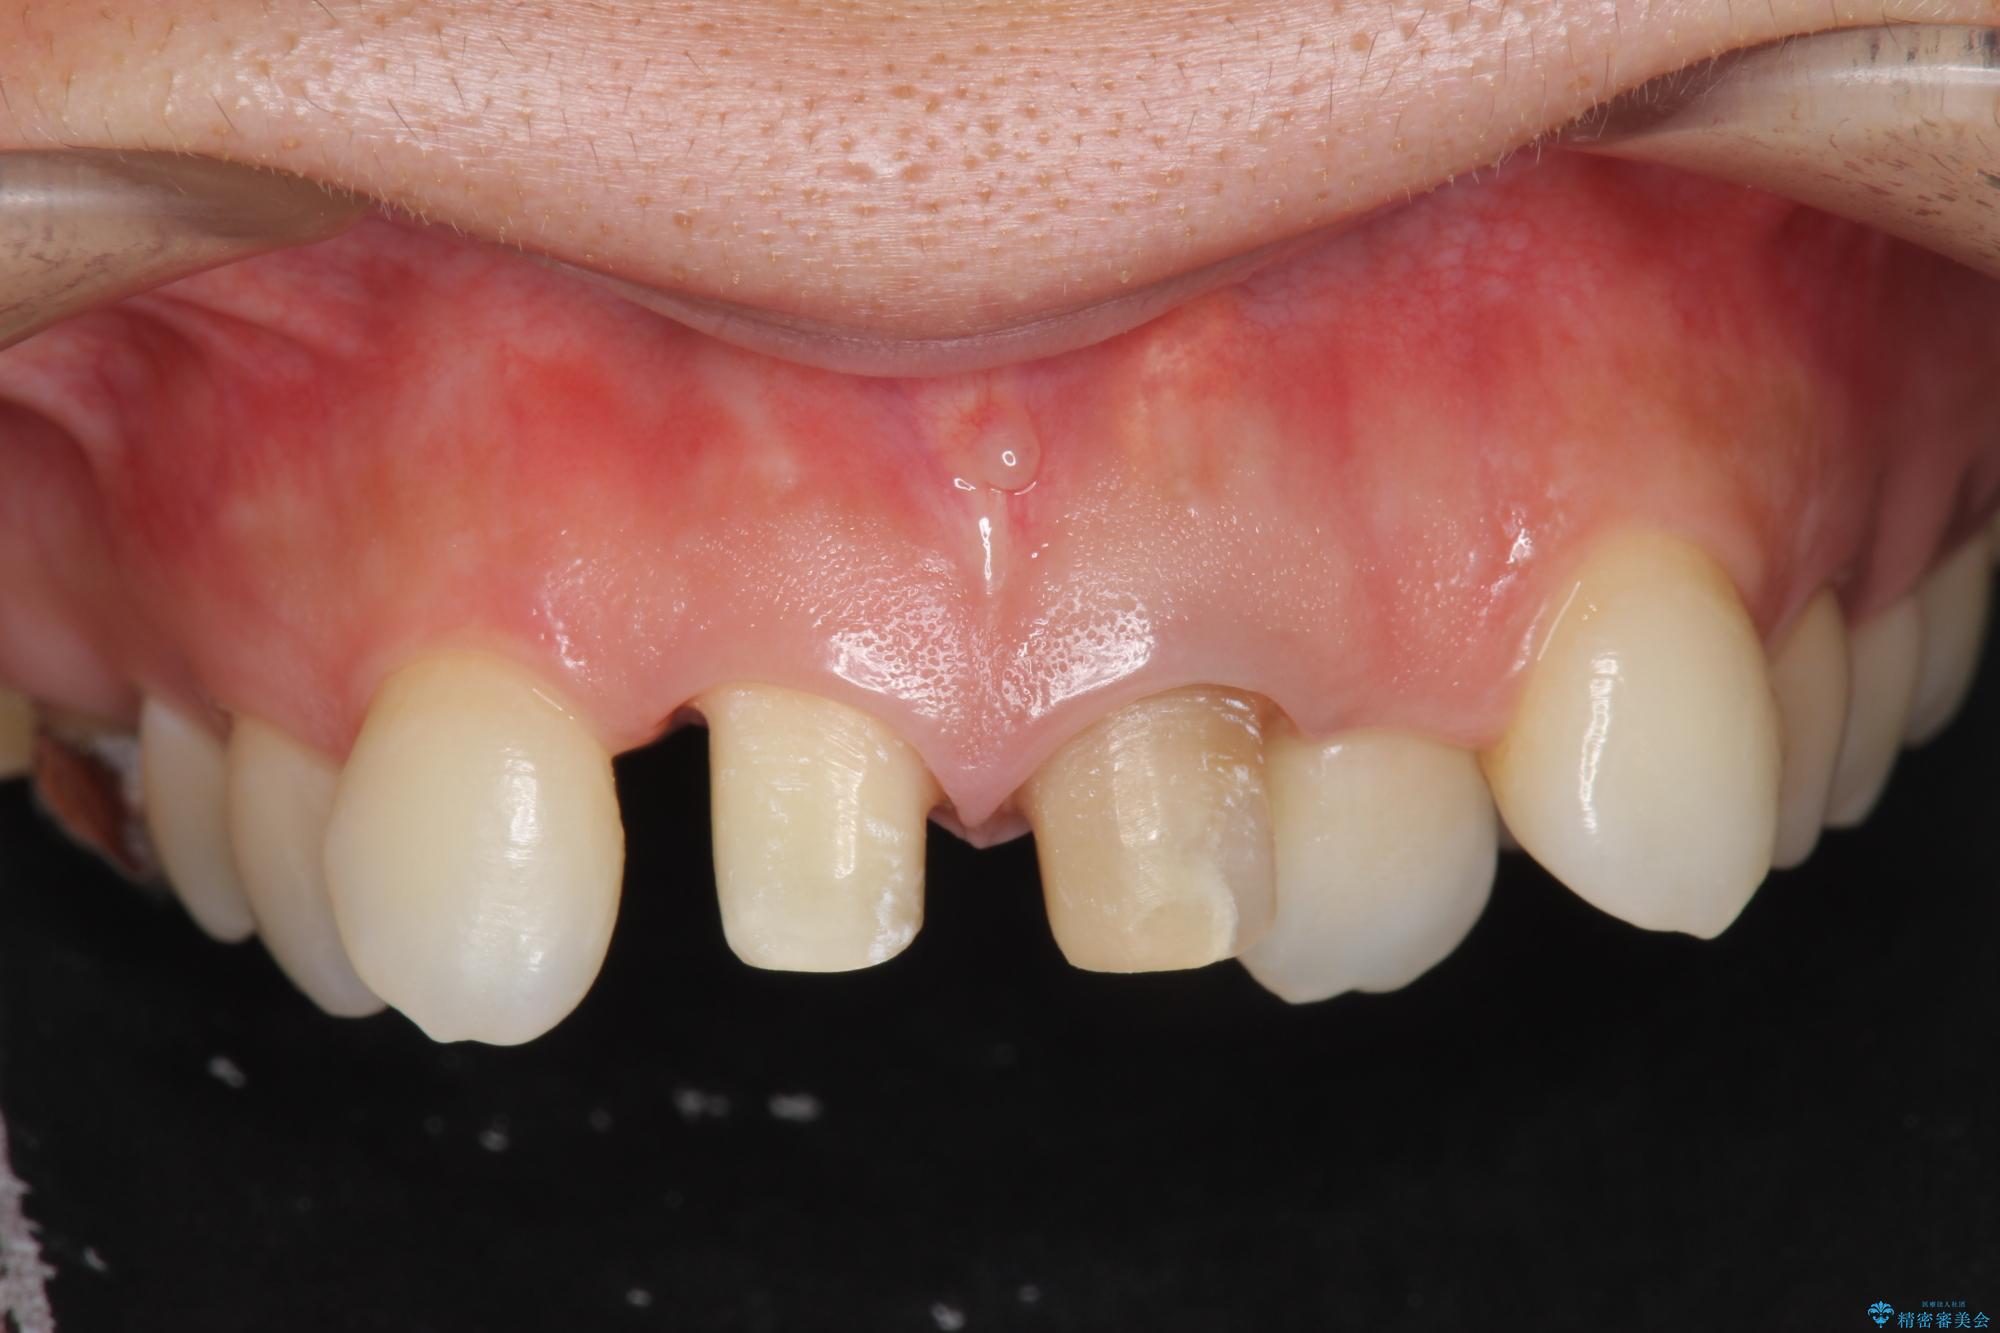

前歯の変色が気になるとご来院された患者様です。

レントゲン検査の結果、以前の根管治療の詰め物が突き出た状態でしたので、まず精密な再治療を行います。同時に、歯磨きがしにくく虫歯の原因になっている右上側切歯を抜歯し、その後、セラミック治療で全体を美しく修復する計画です。

歯磨きがしにくい歯を抜歯することで、今後の虫歯の再発を防ぐ治療計画としました。